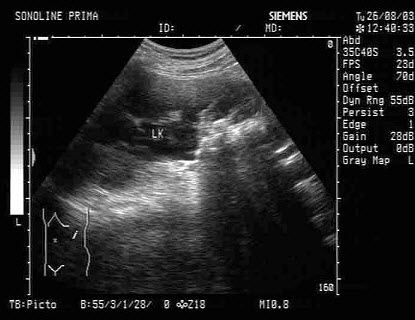

103、单项选择题

男,48岁,上腹胀痛,纳差,血吸虫病多年。结合超声声像图,诊断为()

A.血吸虫肝纤维化

B.脂肪肝

C.细菌性肝脓疡

D.肝豆状核变性

E.肝炎